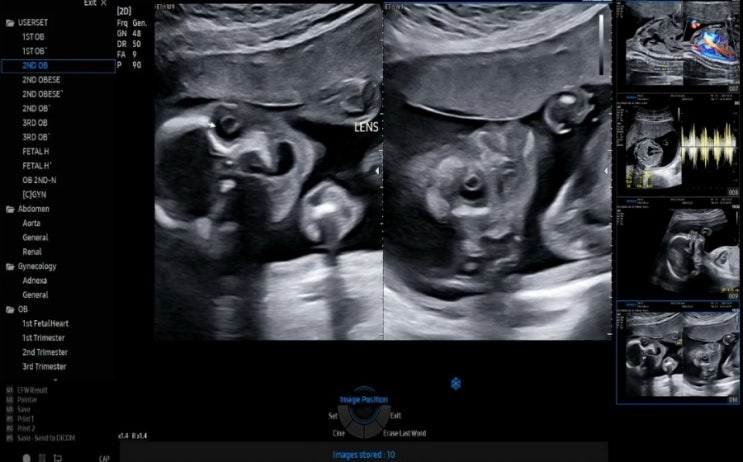

2023.10.20 (20W 1D) 너란 아이를 샅샅히 들여다 보겠다!!!_산전 정밀 초음파 + 독감주사 + 산후조리원 계약까지

정밀 초음파를 보고왔다. 정밀 초음파 검사 태아 기형을 진단하는데 있어 필수적인 검사 20주 정도가 되면 ...